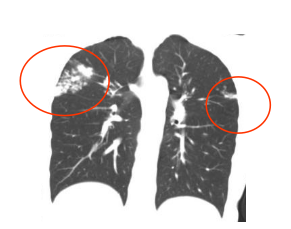

2026年2月,距筛查仅5个月,小东无明显诱因出现咳嗽、低热,自行服药后虽体温恢复正常,但咳嗽持续加重,甚至出现痰中带血丝。经检查,最终确诊为活动性肺结核,不得不办理休学,在长沙市中心医院(南华大学附属长沙中心医院)学生儿童结核科接受长期治疗。

2026年2月,小东肺部CT显示:异常